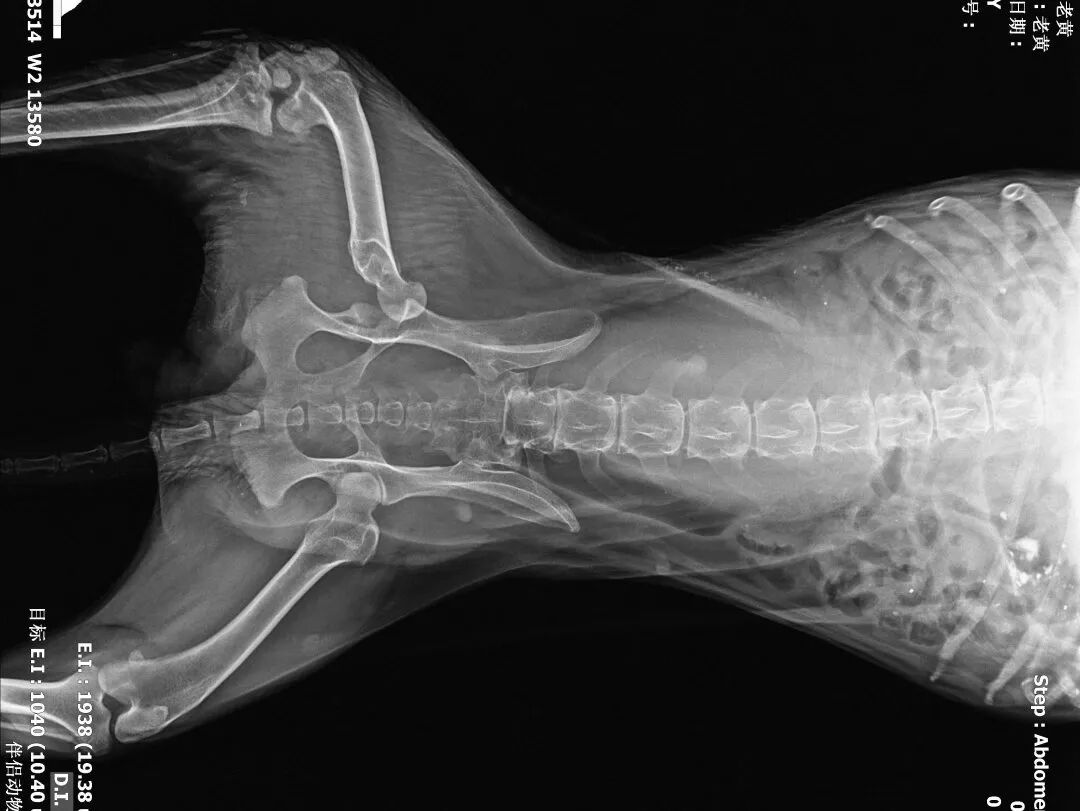

2、血常规、生化、凝血、DR(正侧)

动物拍片腹部怎么摆【病例分享】犬-外科-股骨头切除术_https://www.jmylbn.com_新闻资讯_第6张

术后侧位片

动物拍片腹部怎么摆【病例分享】犬-外科-股骨头切除术_https://www.jmylbn.com_新闻资讯_第31张